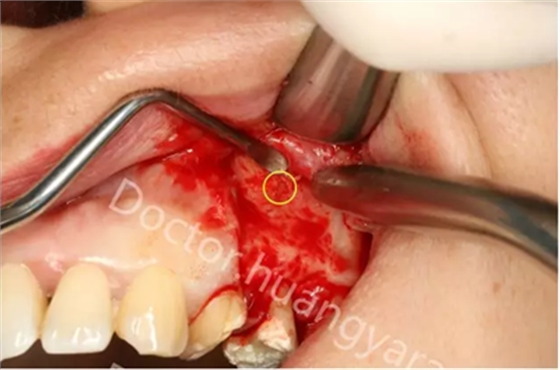

拍攝根尖片檢查,24、25牙根充到位,但考慮到可能是治療過(guò)程中消毒不到位導(dǎo)致,所以重新對(duì)25牙做根管治療,但酸痛感無(wú)減輕,于是考慮到根尖骨穿孔的可能性,與患者溝通后做診斷性翻瓣,翻瓣后發(fā)現(xiàn)根尖處無(wú)頰側(cè)骨板直接暴露,當(dāng)即行根尖切除術(shù),對(duì)位縫合,經(jīng)兩個(gè)月恢復(fù)根尖已無(wú)酸痛感!